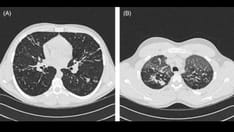

Ciliary ultrastructure, Left, Normal cilium from a healthy individual in which both inner and outer dynein arms can clearly identified. Right, the absence of outer and inner dynein arms in a patient with primary ciliary dyskinesia. Image courtesy of J. Carson, PhD, University of North Carolina.